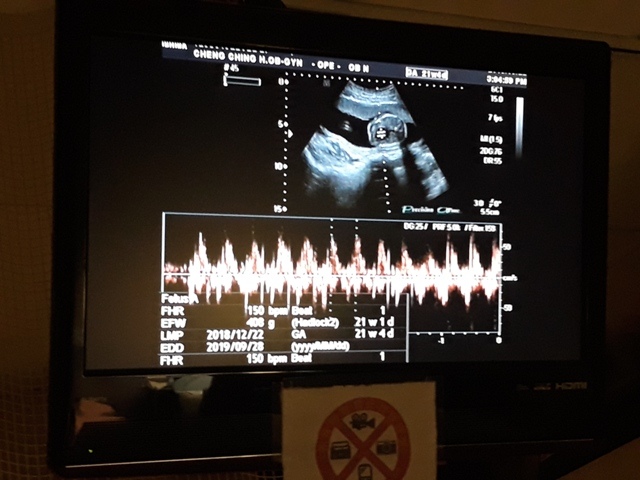

今天的高層次超音波照下來,小飛還蠻健康的,唯獨FL(大腿骨的長度)的成長,比目前實際的天數(21週又5天)還小(超音波照出來是20週又6天),不過還在正常值內,小純聽到這個消息心情有些Blue,問關醫師多喝牛奶能不能改善,關醫師卻叫小純不要喝太多牛奶:「牛奶喝多了,會有牛脾氣。」關醫師也不只一次的表示,希望孕婦不要吃太多,吃太多會讓小寶寶變大,這樣不利於生產,至於FL成長比較慢的事,關醫師說,孩子出生再補給足夠的營養或者運動即可。

| 2019年05月22日 | 53.4mm(28%) | 160.6mm(28%) | 34.6mm(20%) | 408g(69%) | 150 |

| BPD:胎兒頭骨橫徑 AC:胎兒腹圍的長度 FL:胎兒大腿骨的長度 EFW:胎兒的體重 括弧內百分比為較上次產檢的成長比例 | |||||

-

| 日期/項目 | OFD | AFI(4) | HC |

| 2019年05月22日 | 67.7mm | 17.9mm | 198.4mm |

| OFD:胎兒頭寬徑 AFI:羊水指數 HC:胎兒頭圍 | |||